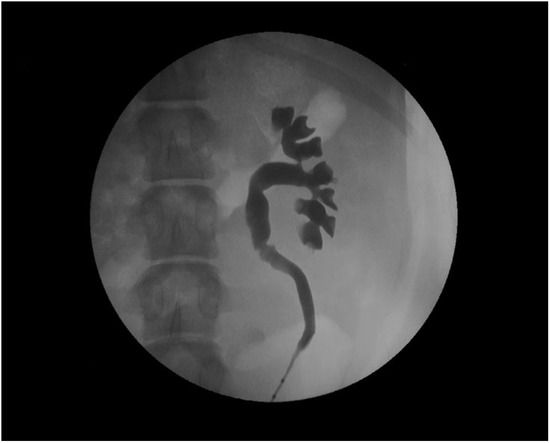

- Tunc, L.; Resorlu, B.; Unsal, A.; Oguz, U.; Diri, A.; Gozen, A.S.; Bedir, S.; Ozgok, Y. In vivo porcine model for practicing retrograde intrarenal surgery. Urol. Int. 2014, 92, 64–67. [Google Scholar] [CrossRef]

- Soria, F.; Rioja, L.A.; Blas, M.; Durán, E.; Usón, J. Evaluation of the duration of ureteral stenting following endopyelotomy: Animal study. Int. J. Urol. 2006, 13, 1333–1338. [Google Scholar] [CrossRef]